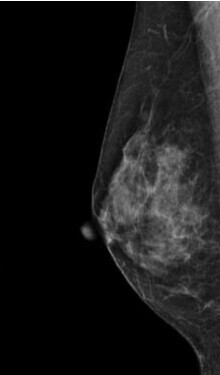

検査結果では、乳房の構成を以下4つに分類してお知らせします。

1.脂肪性

2.乳腺散在

3.不均一高濃度

4.極めて高濃度

3・4に該当する乳房は「高濃度乳房(デンスブレスト)」と呼ばれ、乳腺が白く映るためマンモグラフィのみでは異常が隠れてしまうことがあります。

そのため、マンモグラフィ検査と乳腺超音波検査の併用を強くおすすめします。

症状がなくても、高濃度乳房と判定された方は積極的な併用検診が早期発見につながります。